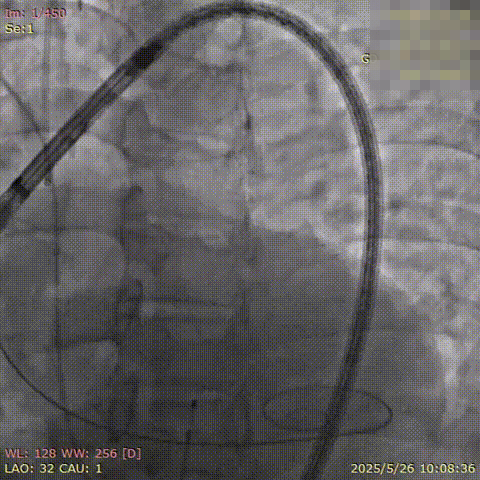

患者在全麻下进行手术,经右侧股动脉建立主入路,直头导丝跨瓣后交换预塑弯形导丝放置于左室。TaurusMax®经导管主动脉瓣系统装载AV29瓣膜,该系统具有“3D双轴”调弯功能,系统过弓跨瓣更加安全顺畅,同时系统在跨瓣后可实现同轴调整,降低术中对导丝操作的依赖,改善瓣膜释放不同轴导致的高低瓣问题,提升瓣膜释放稳定性及血流动力学。瓣膜在调弯状态下一次释放脱钩,瓣膜深度瓣下2mm,形态良好,同轴性佳,DSA下对合缘对齐(CA)结果良好。

主动脉根部造影可见显著造影剂反流,主动脉根部扭转,猪尾初始位于右冠窦;预装AV29瓣膜进行植入。

使用预塑形导丝配合TaurusMax调弯过弓并跨瓣,输送器调弯约70%,左前斜进行投照角度下过弓。

跨瓣后T-Marker形态检查无误,输送器调弯至100%,释放位完全同轴,左侧位观察同轴优秀,极大程度上缓解大横位心因素。

右窦中心位下释放,显影点近1:1:1初步判断CA实现对齐,初始定位0位释放

与常规不可调弯TAVR系统有所不同,TaurusMax系统在完成调弯调轴后,同轴性较好,释放阶段瓣膜展开基本居中展开。首次释放初始定位0位,180次/分起搏后,血压偏高,释放过程中瓣膜上跳。